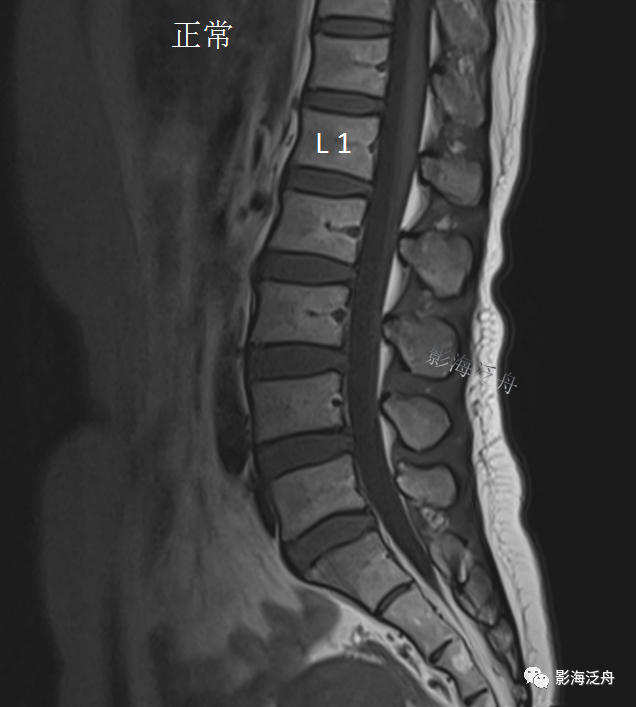

先不着急解开谜底,我们看一个正常片子

正常的腰骶部MR解剖:在脊髓圆锥(红箭)水平以下,椎管内走行的主要是终丝及马尾神经(黄箭),大量脑脊液填充在硬膜囊内(蓝箭头);硬膜囊以外的椎管内只有少量脂肪组织填充(绿箭头)。